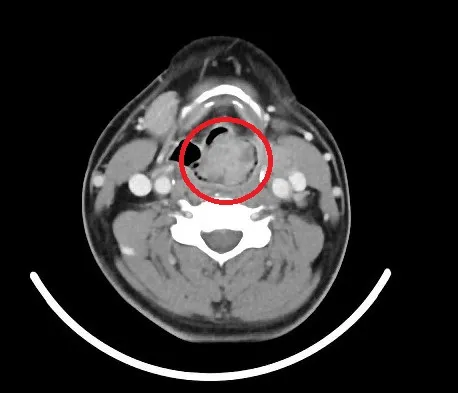

王男喉嚨處發現一顆將近3公分大的腫瘤,喉道僅剩些微的縫隙能維持。院方提供

林奐宇醫師指出,王男到診間就主訴聲音沙啞、吃東西吞嚥困難,而他發現王男講話時已經出現「咻咻」的喘息聲,趕緊安排內視鏡檢查,在喉嚨處發現一顆將近3公分大的腫瘤,喉道僅剩些微的縫隙能維持呼吸,建議做保護性的氣切手術,以維持呼吸暢通,並做腫瘤切片檢查。